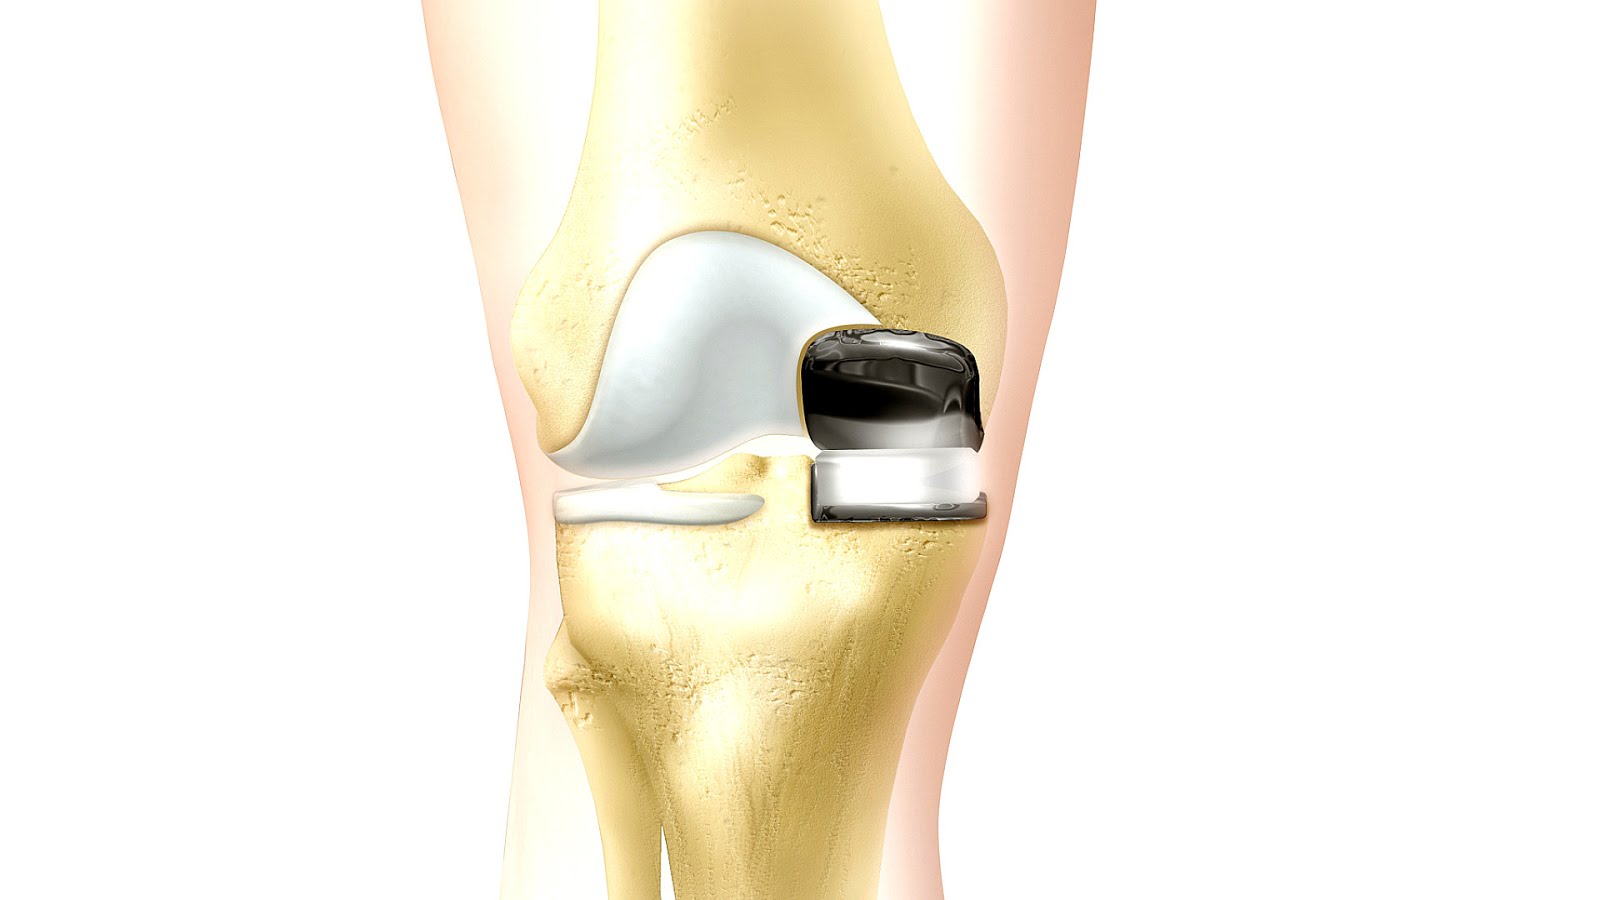

Примеры протезов коленных суставов Zimmer

Раздел: Образы вокруг